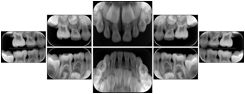

3. A patient in rural Minnesota experiences sudden vision loss and goes to a general ophthalmologist, who acquires OCT images and forwards them electronically along with a Structured Display to a retina specialist six travel hours away. The retina specialist is able to view the images in the standard layout that he is comfortable with, and to confirm that the patient has a choroidal neovascular membrane. He determines that is would be worthwhile for the patient to travel for treatment.

OCT Retinal Study with Cross Section and Navigation Structured Display

Figure OO-4. OCT Retinal Study with Cross Section and Navigation Structured Display